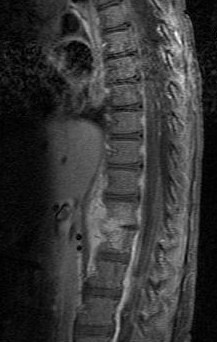

- MRI is gold standard